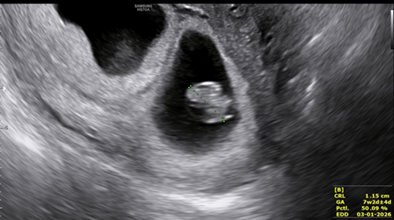

The case of a 27-year-old primiparous women who presented at 7 weeks with features of hyperemesis in a routine pregnancy follow up is presented. No previous ultrasonographic imaging was done. Current ultrasound scan showed a twin live intrauterine pregnancy with thick separating membrane giving a lambda sign. Crown Rump Length (CRL) of fetus A measured 1.32 mm with Fetal Heart Rate (FHR) at 166 Beats Per Minute (BPM) and the CRL of fetus B was 1.15 mm with FHR 154 BPM. It also showed a gestational sac with a fetal pole with CRL 10 mm in the right ovary complicated by a surrounding peri-ovarian hematoma forming a right adnexal mass measuring 57×35 mm. No cardiac activity was seen in this fetal pole (Figure 1 A/B).

The left ovary showed a corpus luteal cyst (Figure 3). The findings were consistent with a twin intrauterine live dichorionic diamniotic pregnancy and a right ovarian pregnancy without cardiac activity.